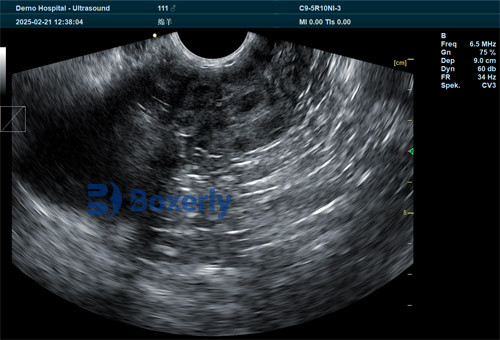

Portable B-mode ultrasound machines produce two-dimensional grayscale images that display the uterus, fetal vesicles, and viable embryos.

Portable B-mode units with 3–5 MHz linear probes are standard for abdominal scanning.

Higher-frequency probes (5–10 MHz) with rectal extensions yield earlier detection but are used less widely.

Identify fluid pocket and fetal vesicle

Detect heartbeat for confirmation

Count fetus(es) to assess litter size

Check uterus for pathological signs